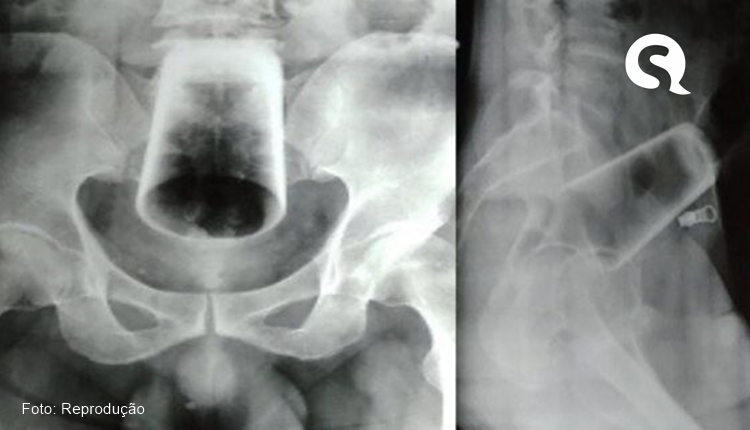

Um homem precisou ser socorrido às pressas e foi levado ao Hospital Regional da cidade de Cáceres, no Mato Grosso, após introduzir um copo de vidro no ânvs.

No entanto, ao chegar ao local, a equipe percebeu a gravidade da situação, pois o copo havia quebrado dentro dele. Ele foi submetido a uma cirurgia, mas seu estado de saúde ainda não foi divulgado.